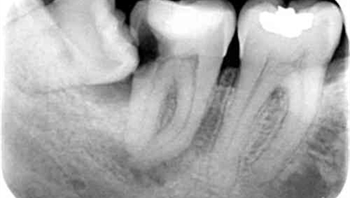

Wisdom teeth often known as third molars are the last teeth to erupt. One usually gets them in late teens or early twenties. However, even instances of eruption in late adulthood are common. If they erupt smoothly and without any interruption, then they can be proved as an asset. But the problem with third molars is that in case they do not erupt properly or are misaligned, they would need to be extracted. If they are poorly aligned, then they can damage the adjacent teeth.

It is also possible that wisdom tooth is impacted. This means that the wisdom teeth remain intact in the soft tissue and partially break or erupt through gums. If they remain partially open, then the chances of bacteria entering the tooth are high which may cause infection & lead to the swelling in the jaw, pain and general illness.

It is not necessary to remove wisdom teeth as long as they are not causing any problem. They would have to be removed if they are impacted or causing crowding. If you do not remove the wisdom tooth, it will be impacted. Your mouth might not provide space for it to erupt as a result it will erupt at the wrong angle which can damage the adjacent tooth.